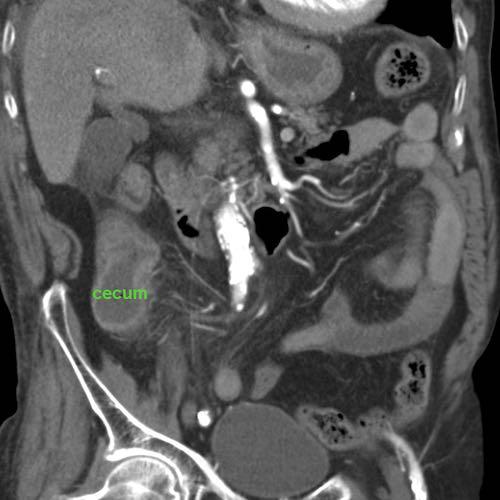

Bệnh nhân nam 85 tuổi này nhập viện với đau khu trú dữ dội, viêm phúc mạc khu trú và CRP 200, lâm sàng nghi ngờ viêm ruột thừa.

Siêu âm cho thấy một vùng nhỏ khu trú gồm mỡ tăng âm bị viêm (đầu mũi tên), chứa một ít dịch (*) và một phản âm khó lý giải (mũi tên trắng).

Chẩn đoán siêu âm dự kiến là viêm phần phụ mạc nối với vùng xuất huyết trung tâm nhỏ.

CT xác nhận thâm nhiễm mỡ khu trú và phát hiện thêm một bóng khí cũng như dày thành nhẹ của một quai ruột non lân cận.

Áp dụng từ gợi nhớ PSI-ABCD, tất cả các nguyên nhân đều được loại trừ, ngoại trừ dị vật sắc nhọn.

Sau khi tìm kiếm có chủ đích, một xương cá được phát hiện tại manh tràng (mũi tên xanh lá trên CT).

Rõ ràng, xương cá này đã gây ra thủng, và sau đó được đẩy đi bởi nội dung ruột non. Bệnh nhân được điều trị bằng kháng sinh đơn thuần và hồi phục hoàn toàn.